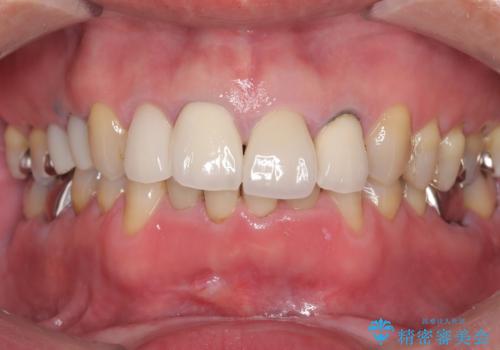

- 治療計画

- 患者様は前歯の審美的な改善を希望されて来院されました。診査の結果、左上1の歯は過去の根管治療により歯根が破折していることが判明し、保存が難しい状態でした。そのため、**長期的な予後を考慮し、抜歯と同時にインプラントを埋入する「抜歯即時インプラント」**を計画。また、隣接する左上2の歯には感染が見られたため、歯根端切除術を同時に行い、感染の除去と治癒を促しました。右上1・2については、セラミッククラウンによる審美修復を行う方針としました。

左上1は抜歯と同時にインプラントを埋入し、骨や歯ぐきの形態を維持しながら治療を進めました。左上2は歯根端切除術により感染部位を除去し、保存治療を実施。右上1・2も含めた前歯4本をセラミッククラウンで修復し、自然な色調と形態を再現しました。治療後は、噛み合わせの安定とともに、美しく自然な前歯を回復することができました。患者様からも「見た目がとても自然で、自信を持って笑えるようになった」と喜びの声をいただきました。